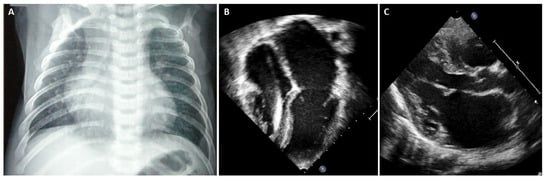

5. When Should I Suspect Restrictive Phenotype on Electrocardiogram or Imaging Techniques?